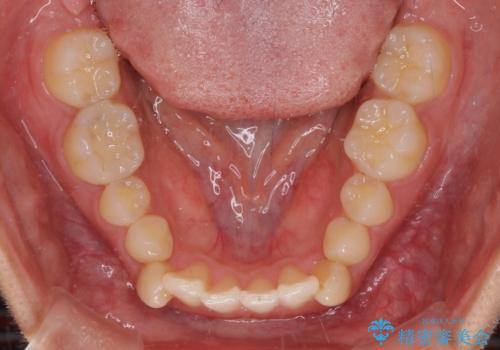

- 下顎の八重歯を気にして来院された患者様です。

マウスピース矯正でもワイヤー矯正でも対応可能であり、マウスピースによる治療を希望されたため、インビザラインを用いることとしました。

下顎前歯にデコボコが集中していたため、顎間ゴムによる後方移動とIPR(歯と歯の間を削ること)により歯列を整えることとしました。

しっかりとマウスピースを装着してくださったおかげで、スムーズに治療を終えることができました。